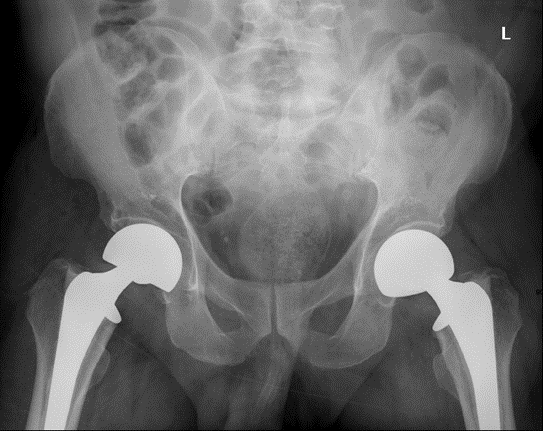

Initial imaging with a pelvic X-ray revealed bilateral displaced femoral neck fractures (Garden Type IV), with evident osteopenia (Figure 1). Degenerative changes in the knees were also noted. Brain CT ruled out acute intracranial pathology, showing only age-related atrophy. Spinal imaging demonstrated grade 1 L5-S1 retrolisthesis with severe disc narrowing and endplate sclerosis.

Figure 1: Pelvic X-ray showing bilateral displaced femoral neck fractures.